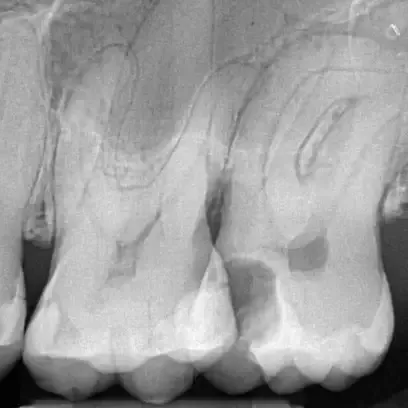

Fall 4: großer interradikulärer Entzündungsherd

Endodontie Fall 4: großer interradikulärer Entzündungsherd

Vor der Behandlung